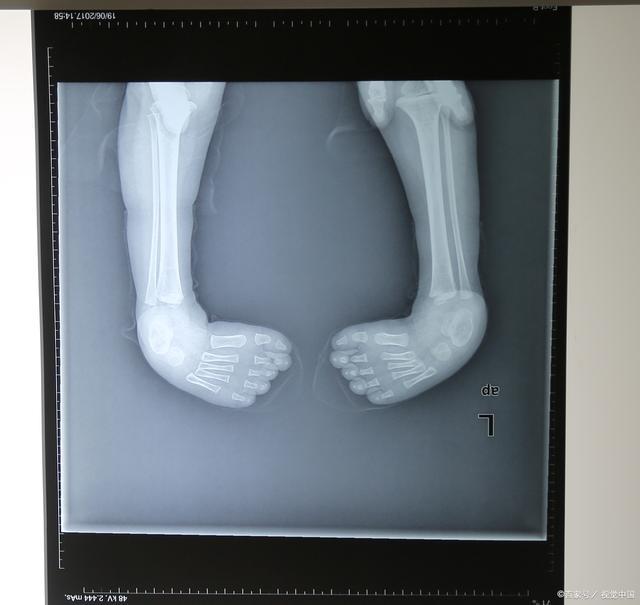

马蹄内翻足可以是单侧肢体受累,也可以是双侧均为马蹄内翻足。如下图所示,为一例双侧马蹄内翻足宝宝。

双侧马蹄内翻足宝宝

足内翻的影像学表现